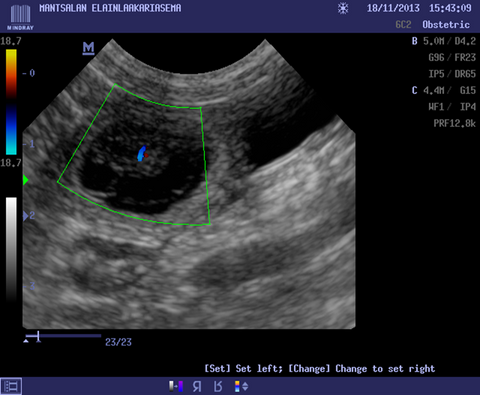

We will cover topics such as when and why these scans are performed, what to expect during the procedure, and their significance at various stages of pregnancy, and what alternatives there are. By the end of this article, you'll have a deep understanding of how canine ultrasound scans can benefit both you and your pregnant dog.

Embryonic deaths are not uncommon. It is reported that in 10-11 % of pregnancies embryonic deaths happen. In this article Merja Dahlbom, Doctor of Veterinary Medicine and ECAR Diplomate, explains Canine Embryonic Death.